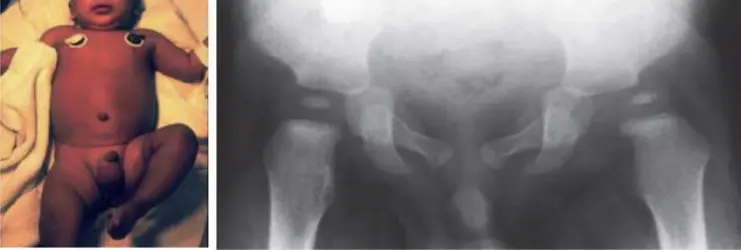

DDH

| DDH Risk Factors (“3 Fs” + others) | * Antenatal: Illnesses/complications during pregnancy, oligohydramnios. |

| * Birth History: Delivery complications, breech presentation (especially frank), APGAR score, C-section vs. vaginal, multiple birth, NICU admission. | |

| * Post-natal: Ever in Pavlik Harness or hip spica cast? | |

| * Family History: DDH or other hip problems? | |

| * First born child? | |

| * Female baby? | |

| * Foot abnormalities at birth? | |